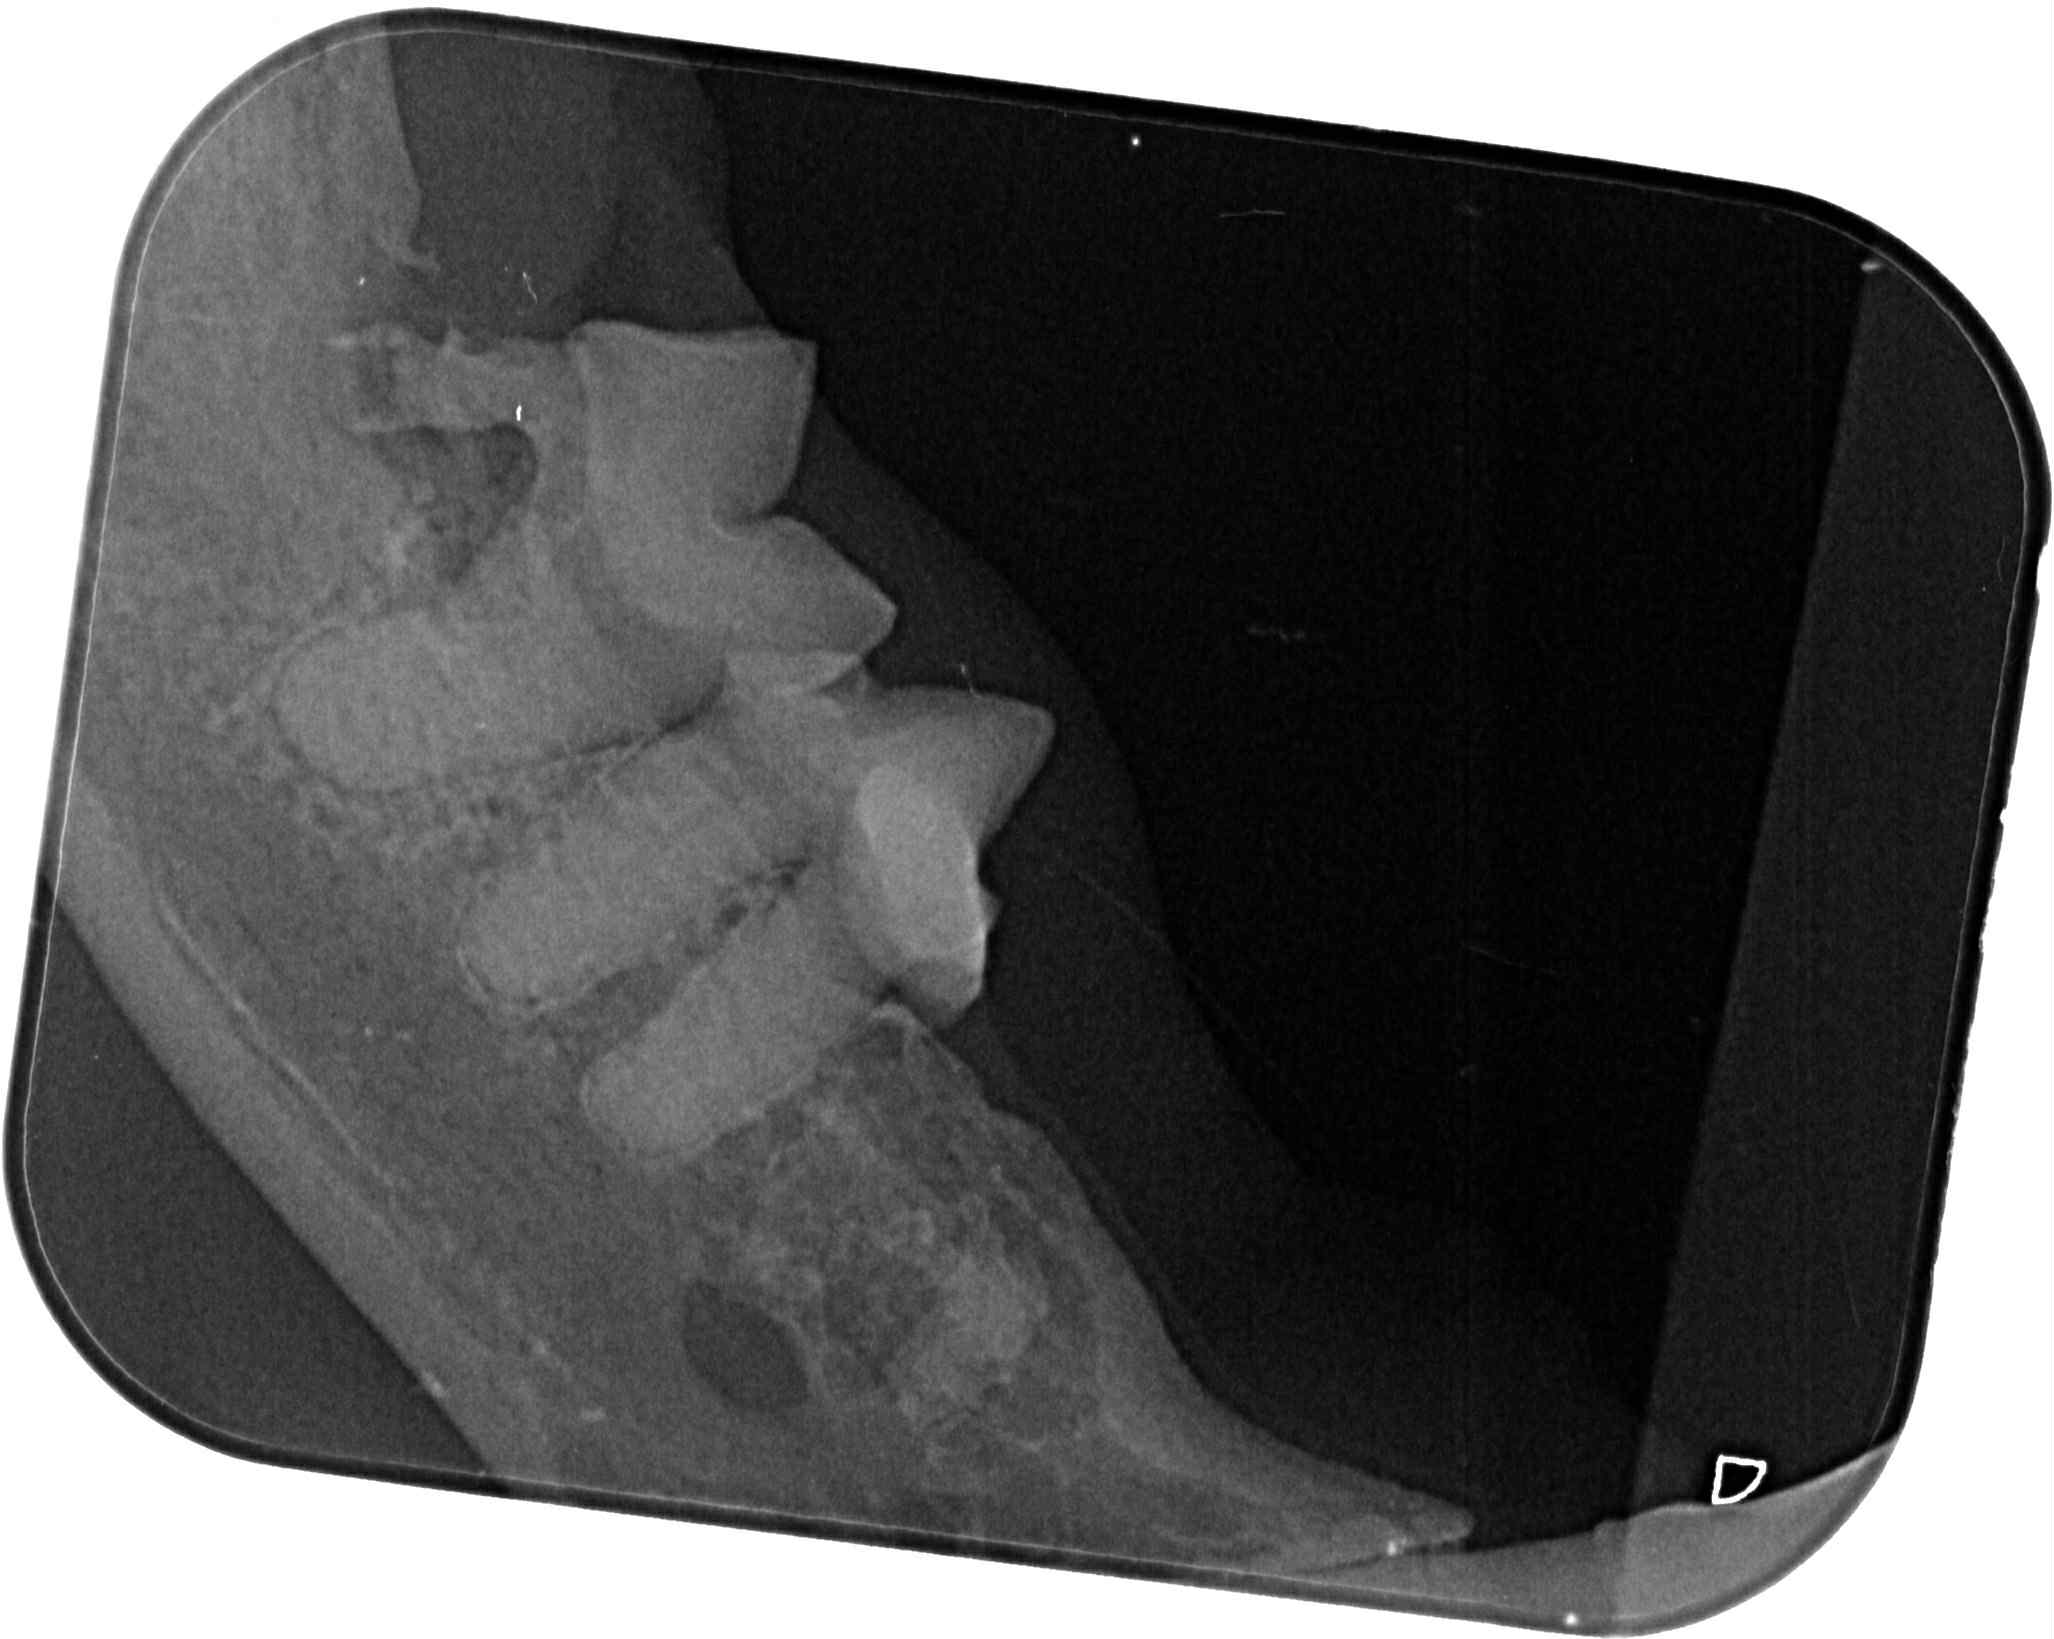

原安置於苗栗貓屋的乖豹於2025年10月與其他貓咪全數移回台北安養之家後發現體型逐漸消瘦,且背上有一顆顆肉瘤以及牙齒有鬆動的狀況,於是安排2025年11月28日於沐恩看診,醫師表示整體狀況還不錯,背上粉瘤為良性,主要是牙結石嚴重,研判體重下滑應與此有關,需盡快安排牙周手術。後再於同年12月17日進行牙周手術,後面的臼齒、2顆下門牙及上顎那一顆不好犬齒都移除,保留下面兩顆犬齒,同時背部腫塊偏良性因此暫不切除。本筆醫助是自2025年11月28日至2025年12月17日間於沐恩醫院的費用,包含看診各項檢驗、牙周手術及用藥。

2025/12/17乖豹 沐恩牙周手術

一、看診說明

手術還算順利,血壓稍微比較不容易穩定,

目前後面的臼齒、2顆下門牙及上顎那一顆不好犬齒都移除了,

下面兩個犬齒的狀況還不錯,所以還是保留下,為了縮短麻醉時間。

皮膚的腫塊看起來外觀偏良性,所以沒切除。

目前看起來,他的咬合是比較正常的,

有可能不會咬到上顎,因為本來就已經有一邊沒有上門牙了,

理論上不會對生活有影響,另外他的下顎聯合原本就是鬆的,

所以會一個伸縮的彈性,對上顎影響相對減少

下顎聯合鬆的意思就是兩側下顎骨會些微的上下晃動。